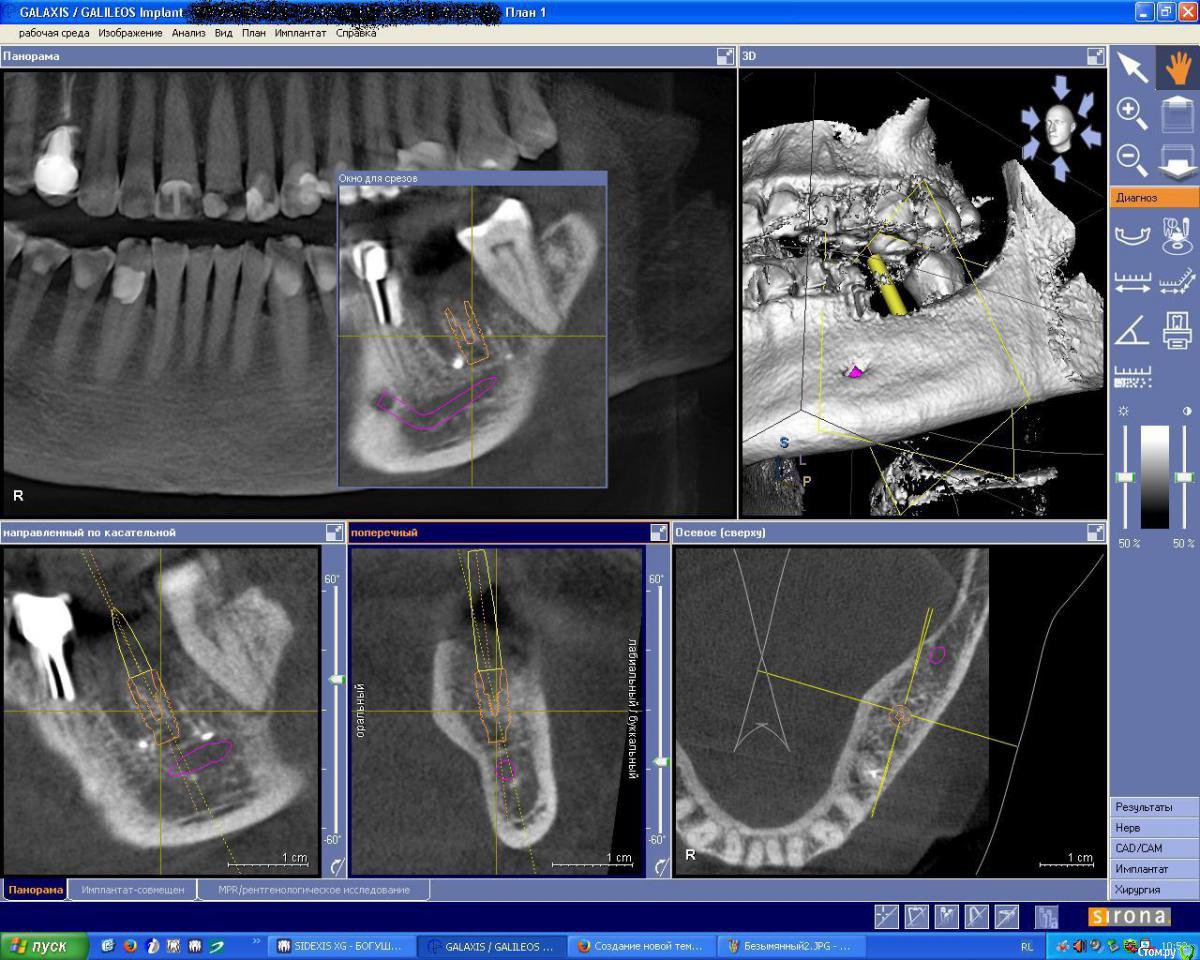

IshIm0 Опубликовано 12 августа, 2015 Поделиться Опубликовано 12 августа, 2015 (изменено) Добрый день коллеги, помогите определиться с тактикой лечения пациента на имплантацию. 18.04.15 Пациентке удалён зуб 36 с выпиливанием корней и полуторачасовым мучением - зуб буд-то анкилозировался с костью. Заживало всё не айс, сгусток вымылся, пища забивалась. Прошло 4 месяца - в полости рта как ни странно все хорошо, лунка под плотной бледно-розовой слизистой, кость при пальпации плотная, широкая. Жалоб не предъявляет - говорит давай имплантат, настроена позитивно. Далее на КТ определяется оставшийся пломбировочный материал, в лунке дистального корня зуба 36 пломбировочный материал лежит фактически на ничнежелюстном нерве. Планирую поставить ICX Ø 4,1 x 10mm, в межкорневую перегороду, уйти немного язычнее, но опасаюсь не даст ли мне этот пломбировочный материал воспалительную реакцию в последствии.Интересуют ваши мнения по поводу данной клинической картины!Позиционирование имплантата на КТ верно? (на КТ Astra 4.5 х 9 mm) Изменено 12 августа, 2015 пользователем IshIm0 Ссылка на комментарий